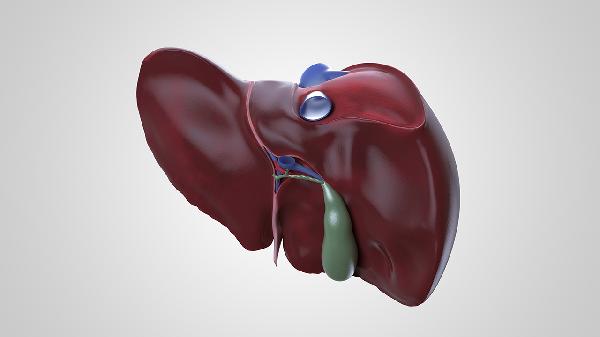

一、肝脏功能异常会拖累大脑

1、代谢废物堆积影响认知

肝脏负责分解体内毒素,当它的工作效率下降时,氨等有害物质会通过血液循环到达大脑,干扰神经细胞正常活动,出现类似"脑雾"的状态。

2、供能机制出现紊乱

这个器官参与血糖调节,功能受损会导致大脑能量供应不稳定,直接影响记忆力和专注度,就像手机电量忽高忽低时容易卡顿。